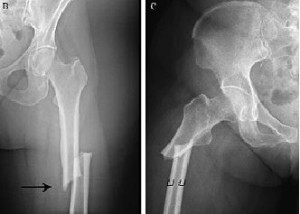

No se está tratando bien la osteoporosis luego de la fractura de cadera

Un estudio encuentra que menos del 10% de los pacientes había iniciado tratamiento para osteoporosis luego de 6 meses de la fractura, a pesar de los beneficios demostrados de los fármacos en esta indicación. JAMA Network Open, 20 de julio de 2018